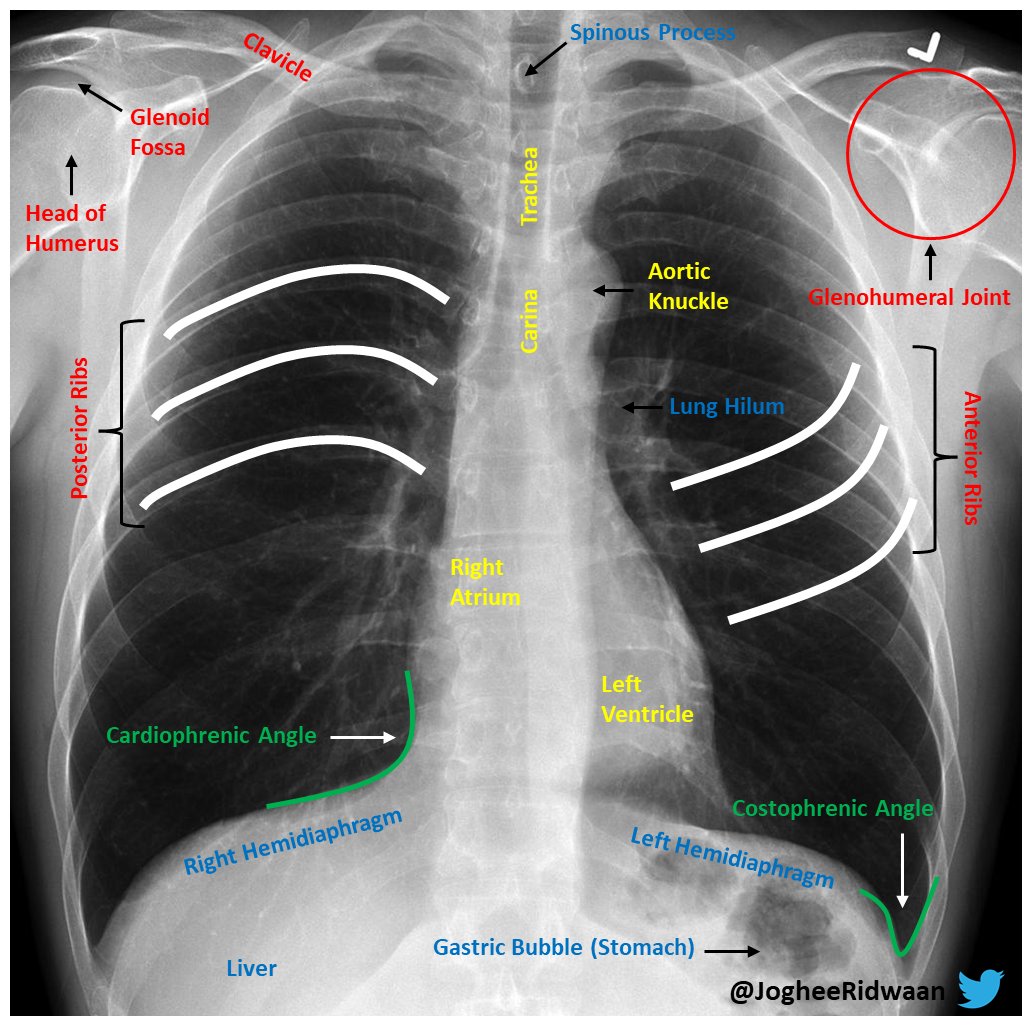

Normal Chest Xray Labeled